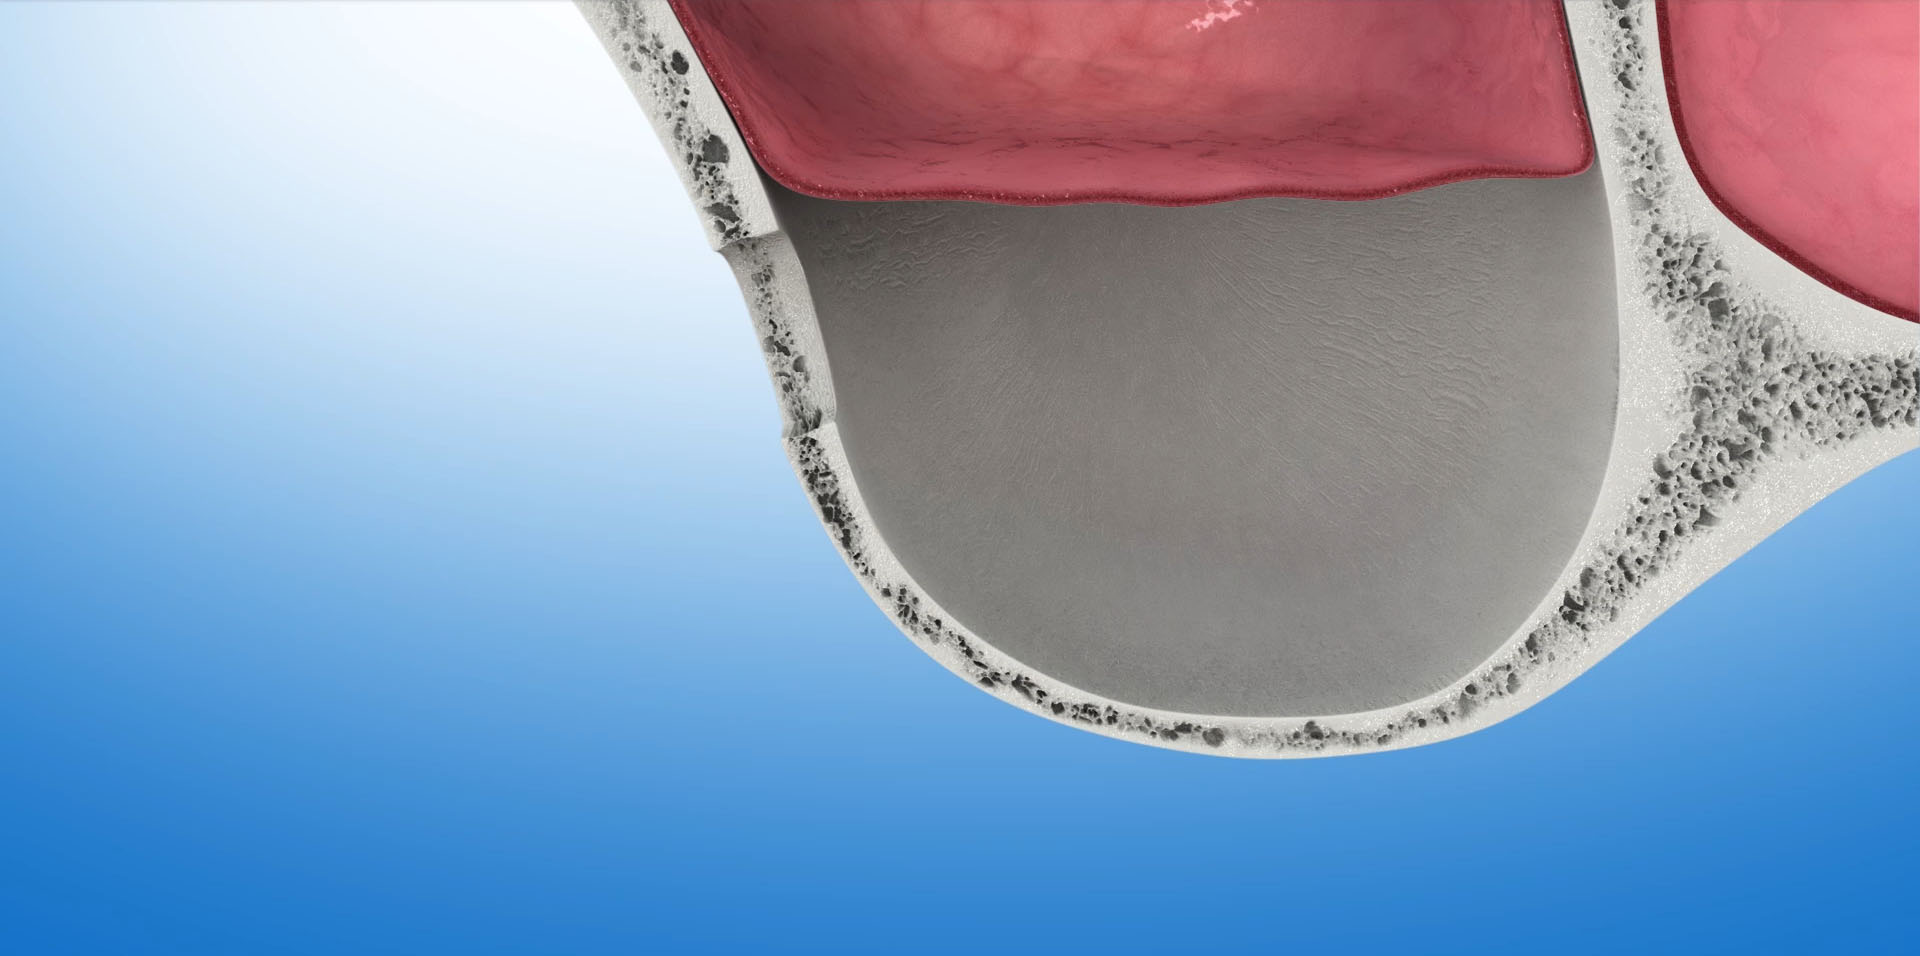

Podniesienie dna zatoki szczękowej

Miejscem, w którym bardzo często spotykamy się z deficytem kości uniemożliwiającym implantację są tylne obszary szczęki górnej. Powodem tego jest znajdująca się po obu stronach trzonu szczęki – zatoka szczękowa (sinus maxillaris). Jest to wypełniona powietrzem przestrzeń w kształcie trójściennej piramidy, której podstawa skierowana jest do dołu. W trakcie życia objętość zatoki powiększa się – następuje jej pneumatyzacja. Utrata zębów w obszarze znajdującym się bezpośrednio pod zatoką szczękową, następujący w związku z tym zanik kości oraz postępująca pneumatyzacja bardzo często uniemożliwia bezpośrednią implantację. Musi być ona poprzedzona zabiegami odbudowującymi kość.

Zabiegiem operacyjnym, którego efektem jest odbudowa kości umożliwiająca implantację w tej okolicy szczęki jest- podniesienie dna zatoki szczękowej -sinus lift. Przeprowadzony po raz pierwszy w 1975 roku, dzisiaj jest bardzo bezpiecznym i przewidywalnym zabiegiem, dającym bardzo dobre wyniki w leczeniu implantologicznym. W zależności od stopnia zaniku tkanki kostnej, która znajduje się pomiędzy zatoką szczękową a jamą ustną zabieg podniesienia dna zatoki szczękowej wykonywany jest dwoma metodami: otwartą lub zamkniętą.